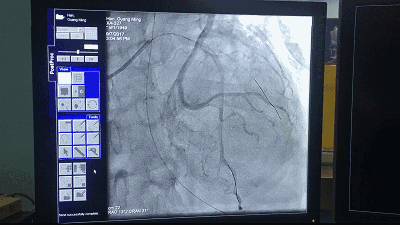

(图为介入手术影像)

冠状动脉介入手术(pci)

接下来置入支架(图17和图18),高压后扩(图19),手术最后的结果满意(图